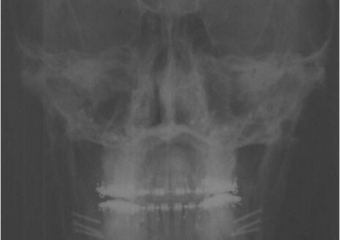

Telerradiografia frontal após a cirurgia